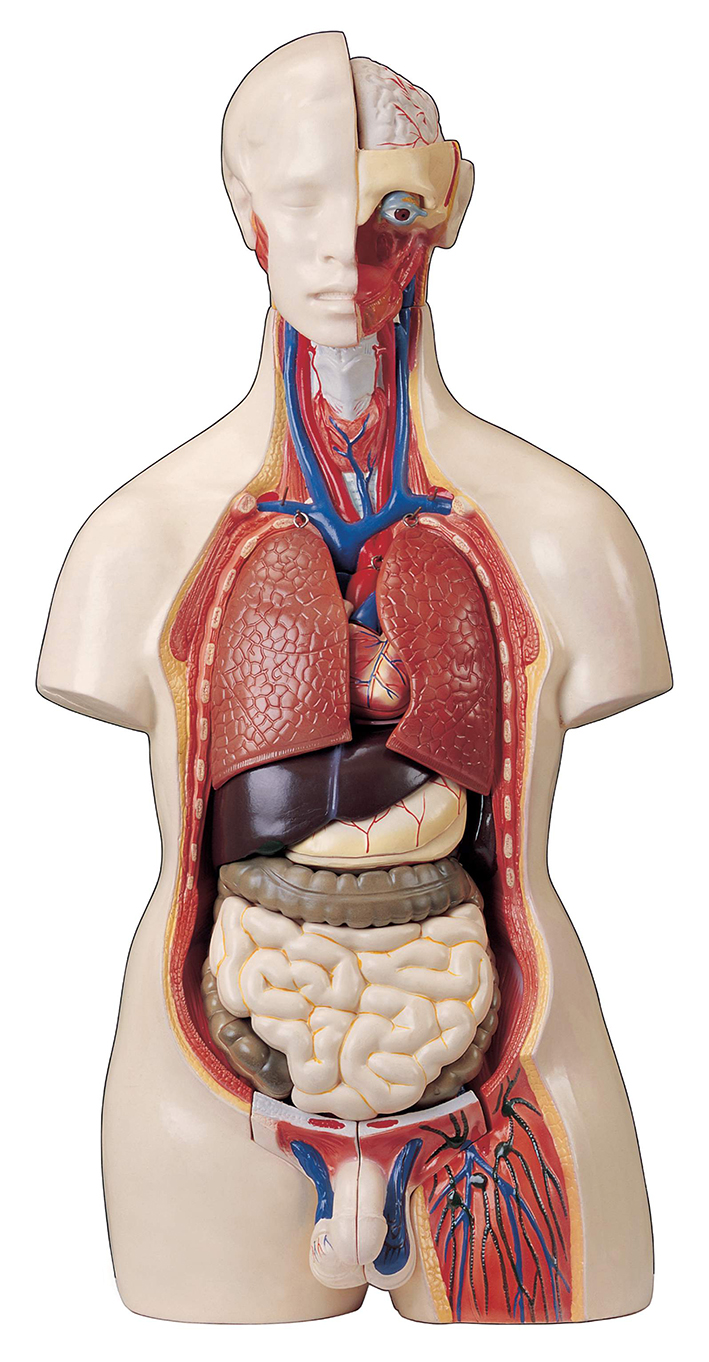

عکس کلیه در بدن

عکس کلیه در بدن. اگر پشت یا پهلوی شما آسیب ببیند مثل برخورد ضربه ممکن است فکر کنید که کلیه هایتان درد می کنند. مقدار و نسبت ترکیب این اخلاط در بدن هر شخصی و در اندامهای. کلیه گ رده ها1 از اندام های درونی بدن انسان به صورت یک جفت عضو لوبیایی شکل در طرفین ستون فقرات روی جدار پشتی شکم و بیرون از حفره صفاق قرار دارند. ک لیه ق لوه میز یا گ رده یکی از اندام های درونی بدن انسان و برخی دیگر از جانداران است.

کلسیم و فسفر که برای تشکلی استخوان لازمند کمک می کنند مواد. کلیه ها با تولید ادارد در دفع مواد زاید تعادل الکترولیتی تنظیم هورمونی تنظیم فشار خون و هوموستازگلوکز نقش دارند. آناتومی کلیه انسان در بدن انسان به این شکل است که کلیه ها دو عضو لوبیایی شکل در دستگاه ادراری بوده و به دفع مواد زائد به صورت ادرار کمک می کنند. یکی از مهم ترین وظایفی که کلیه ها در بدن بر عهده دارند پاک کردن و تصفیه خون از زباله هاست.